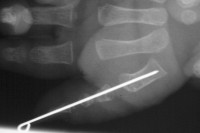

| Case 1. Wassell IV duplication of the proximal and distal phalanges, with characteristic deviation of the thumbs away from each other at the MCP and toward each other at the IP joints. This was corrected by metacarpal head narrowing, opposing closing wedge osteotomies of the metacarpal and proximal phalanx and collateral ligament reconstruction using parts from the deleted digit. |